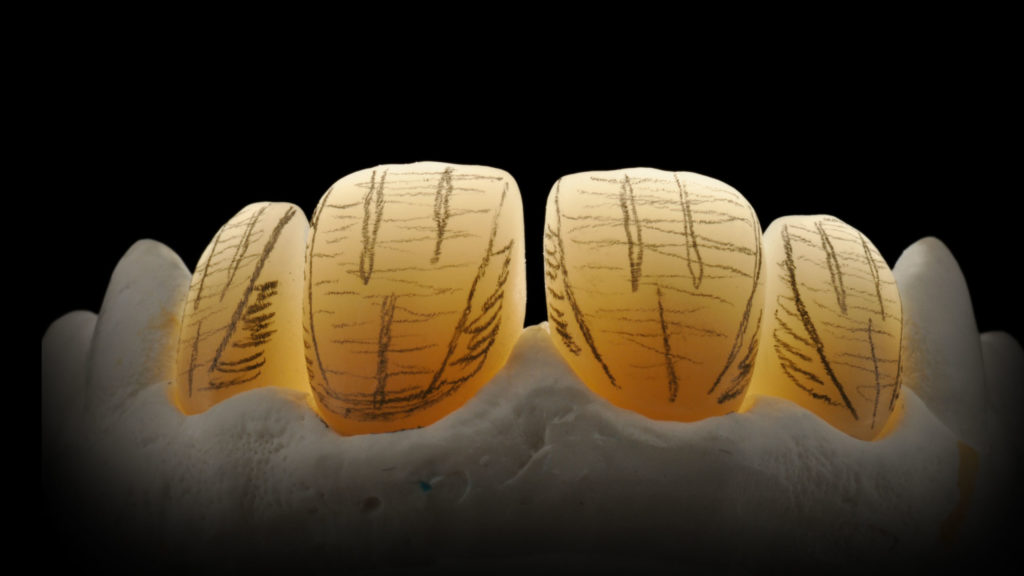

Wenn es eine ästhetisch weniger anspruchsvolle Versorgung zu kreieren gilt, so bietet sich eine vollanatomische Lösung an, für das das neue Katana Zirkonoxid mit einer „Ultramikro-Schichttechnik“ kombiniert wird. Hierfür kommen dann die neuen Cerabien ZR FC Paste Stains zum Einsatz – pastös eingestellte Malfarben, mit denen eine dreidimensionale Farbwirkung erreicht wird (Abb. 3).

Vollanatomische Kronenkörper

Eine „Zero-Cut-back-Technik“ wird beispielsweise verwendet, wenn die CAD/CAM-gestützt designte und gefräste Morphologie vollständig zum Einsatz kommt. Die ästhetische Vollendung wird bei dieser Variante mit einer innovativen und minimalen Ultramikro-Schichttechnik und Cerabien ZR FC Paste Stains (Pastenmalfarben) erreicht (Abb. 7).

Bevor wir die Farbe finalisieren und korrigieren, werden die Oberflächen der Zirkonoxidkronen entsprechend eines morphologischen Plans (Abb. 33) nachbearbeitet und mit einer entsprechenden Textur versehen (Abb. 34a bis e).